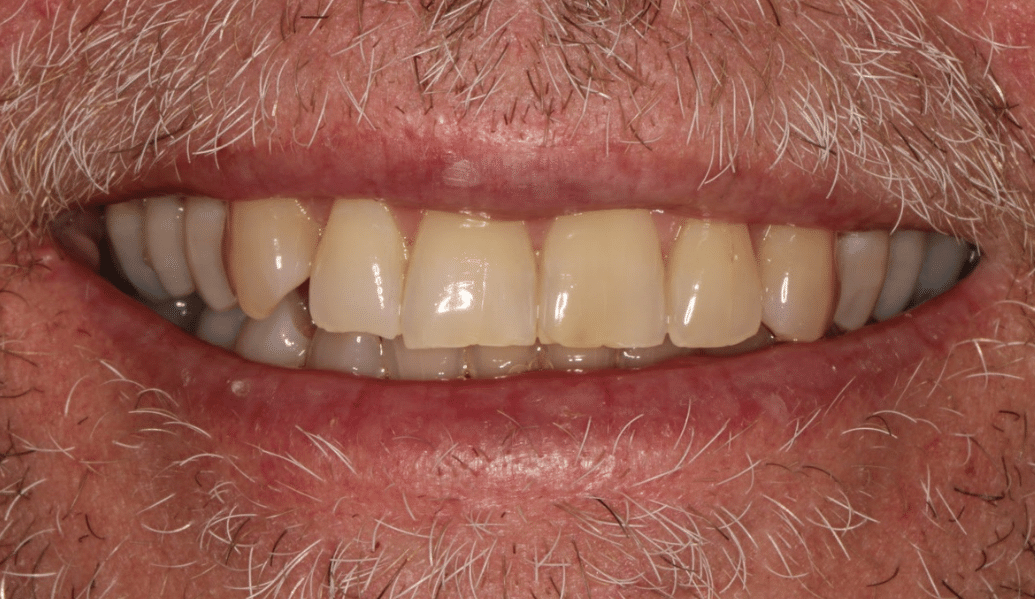

learn moreDelivering life-changing smiles and ensuring excellent dental health.

learn moreDental implants and us – together we can recreate a naturally beautiful smile.